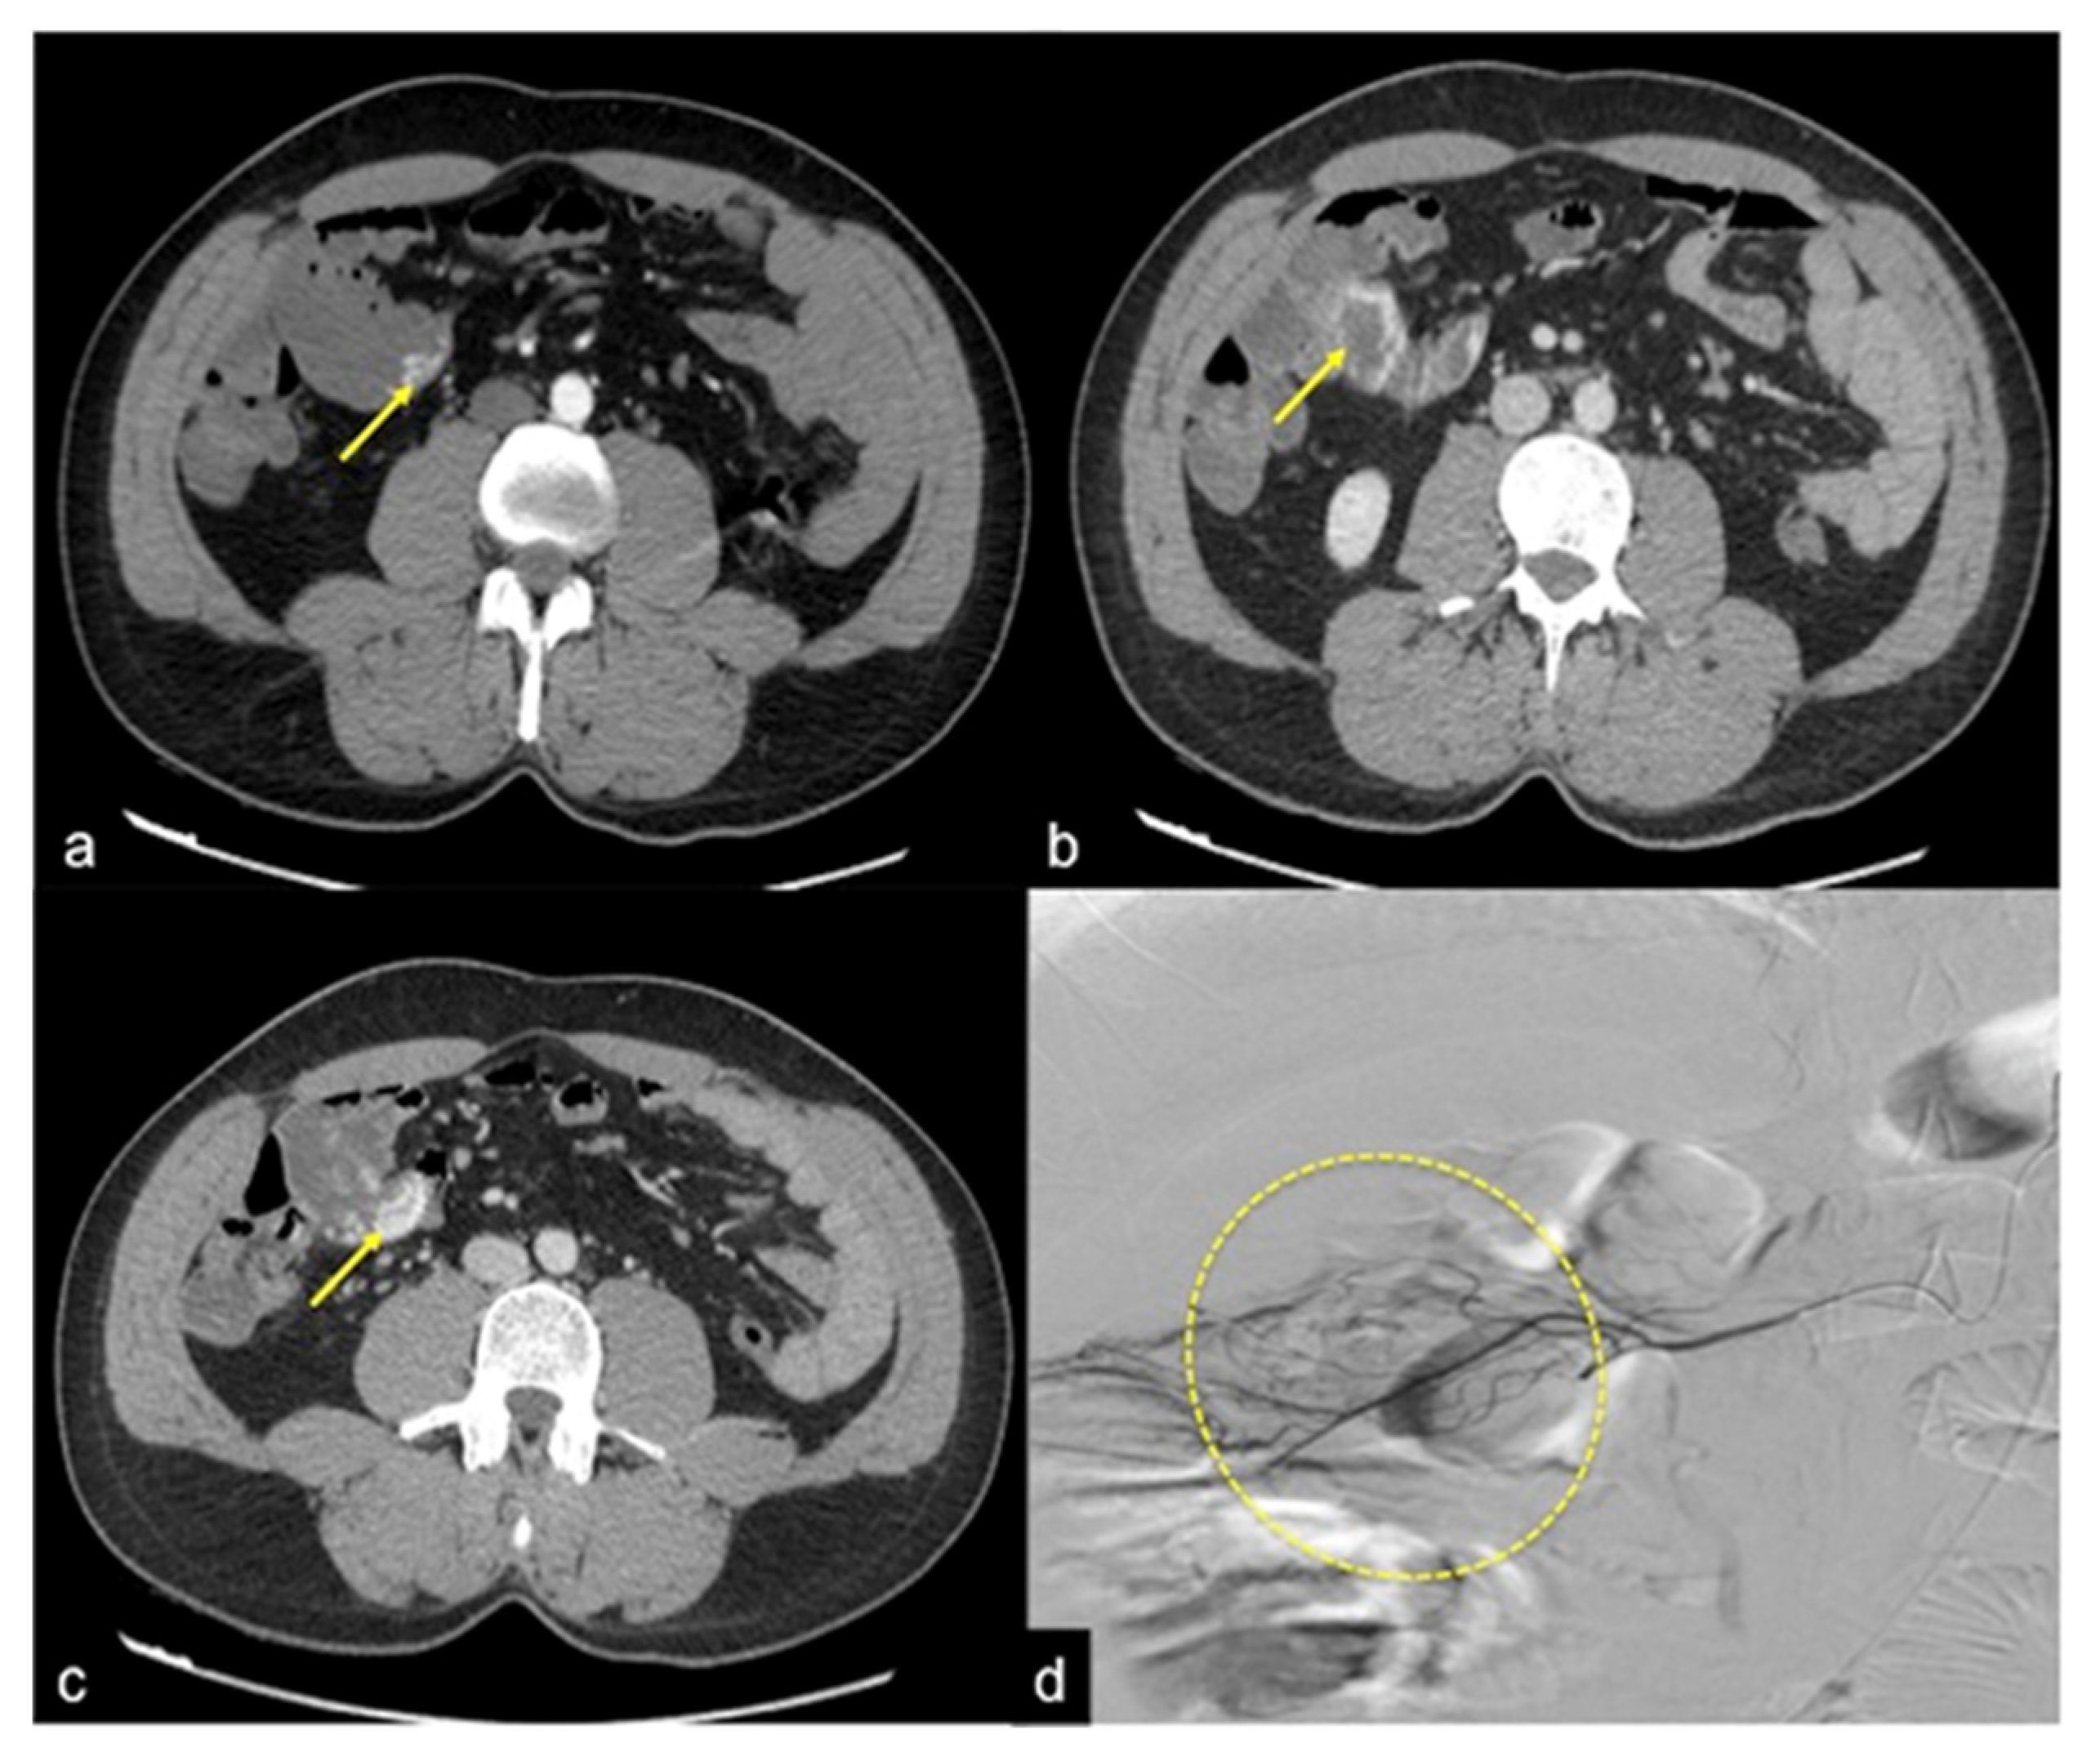

| Colorectal Cancer/Polyps (Figure 6, Figure 36, Figure 37 and Figure 38) | Bowel obstruction with or without bleeding. | Adenocarcinoma: irregular wall thickening with or without stenosis [25]; Polyps: mass-forming protrusions in the intestinal lumen with vascularised peduncle. |